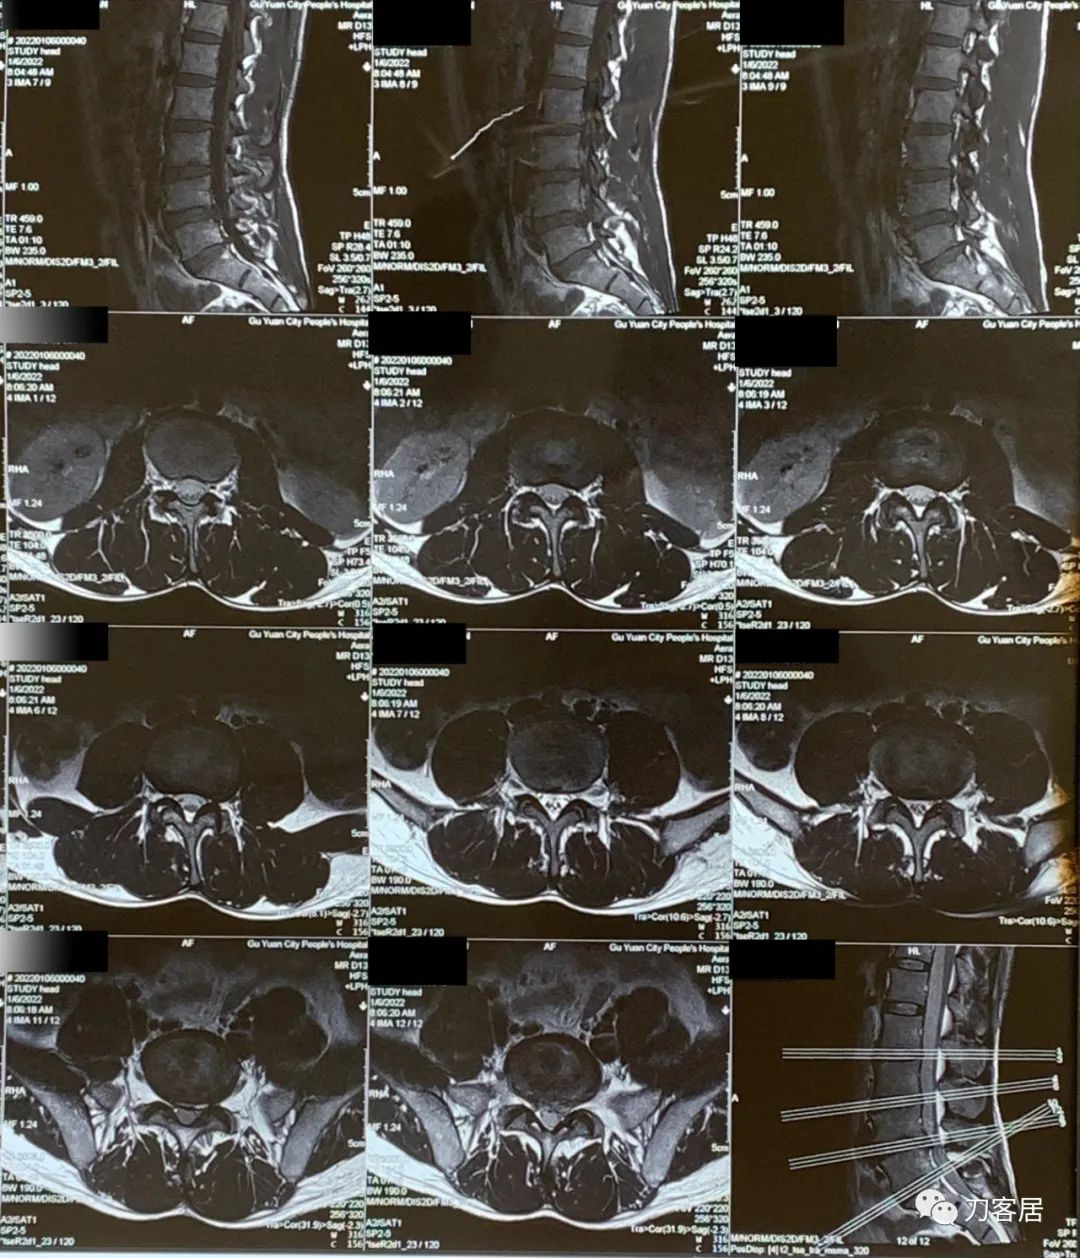

当地医院就诊时,考虑为腰椎间盘突出症,让患者做了腰椎MRI。患者来就诊时带着当地医院给做的腰椎MRI。在腰椎MRI上可见有腰4-5、腰5骶1椎间盘突出,但患者的临床表现有符合椎间盘突出之处,比如左臀部至足背抽痛,但行走不稳,容易摔跤,没法用腰椎间盘突出来解释,所以,就推荐患者到其他医院就诊。

图1. 20220106当地医院腰椎MRI01

图2. 20220106当地医院腰椎MRI02